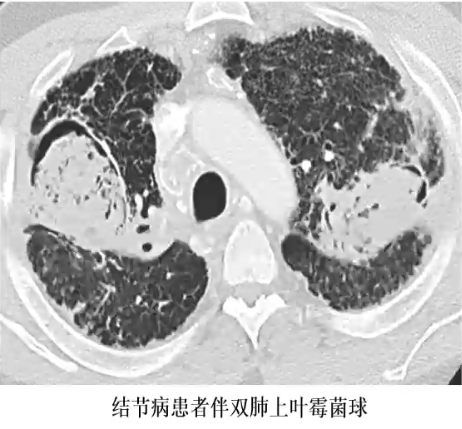

❖ 先前存在的空洞内出现的圆形或类圆形、软组织密度的真菌球

❖ 与结核和结节病关系密切

❖ 洞内肿块可移动,与洞壁之间可见透亮间隙(空气新月征或气环征)

❖ 曲菌球常造成洞壁和邻近胸膜增厚